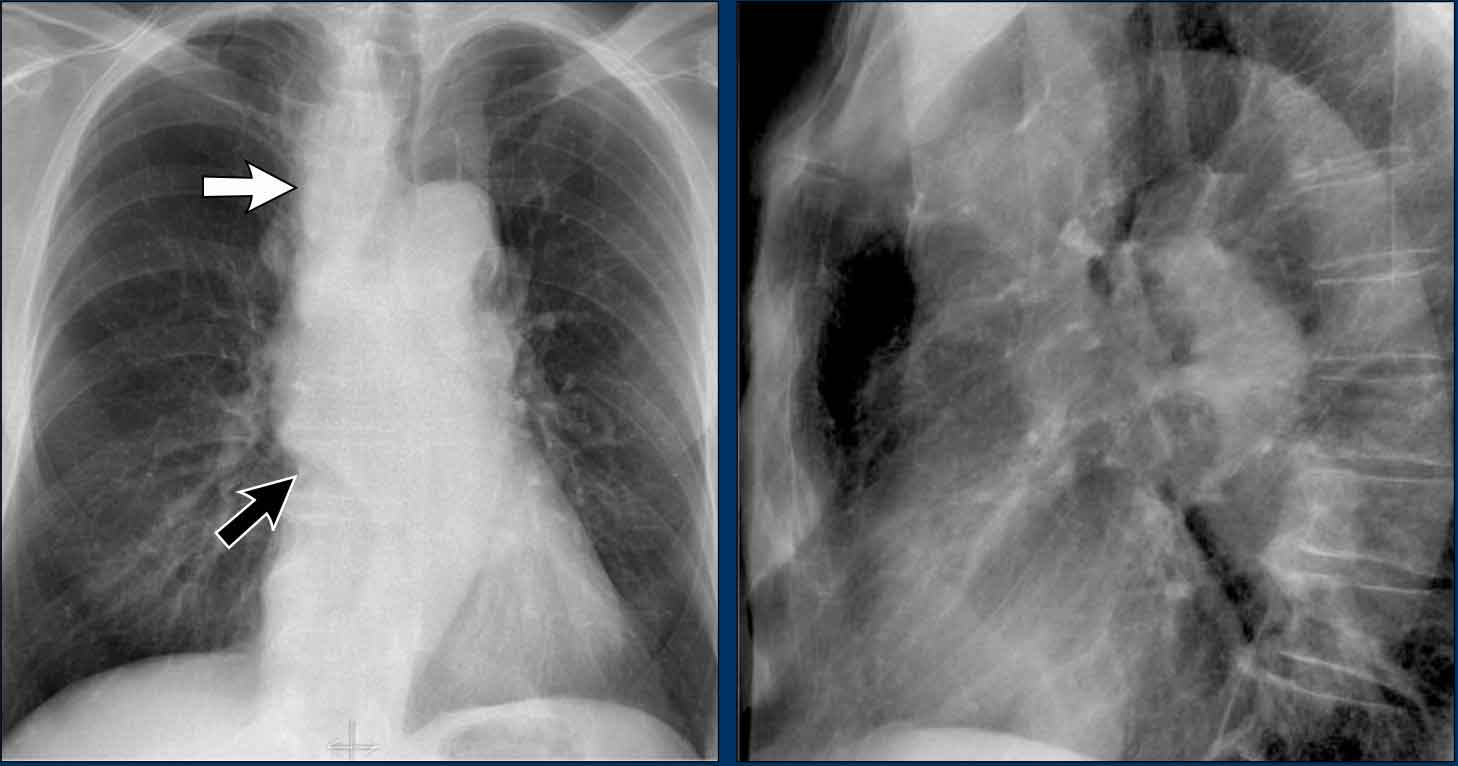

Hodgkin lymphoma. Hodgkin lymphoma.

Mediastinal Masses on Lateral View

When the superior mediastinum appears widened on the PA view, the lateral view is useful to localize the abnormality.

• A soft tissue density in the retrosternal space narrows the differential diagnosis to anterior mediastinal masses, commonly remembered as the "4 Ts":

• Thymoma

• Teratoma (germ cell tumors)

• Thyroid mass

• Terrible lymphoma

In this case, the patient was diagnosed with Hodgkin lymphoma.